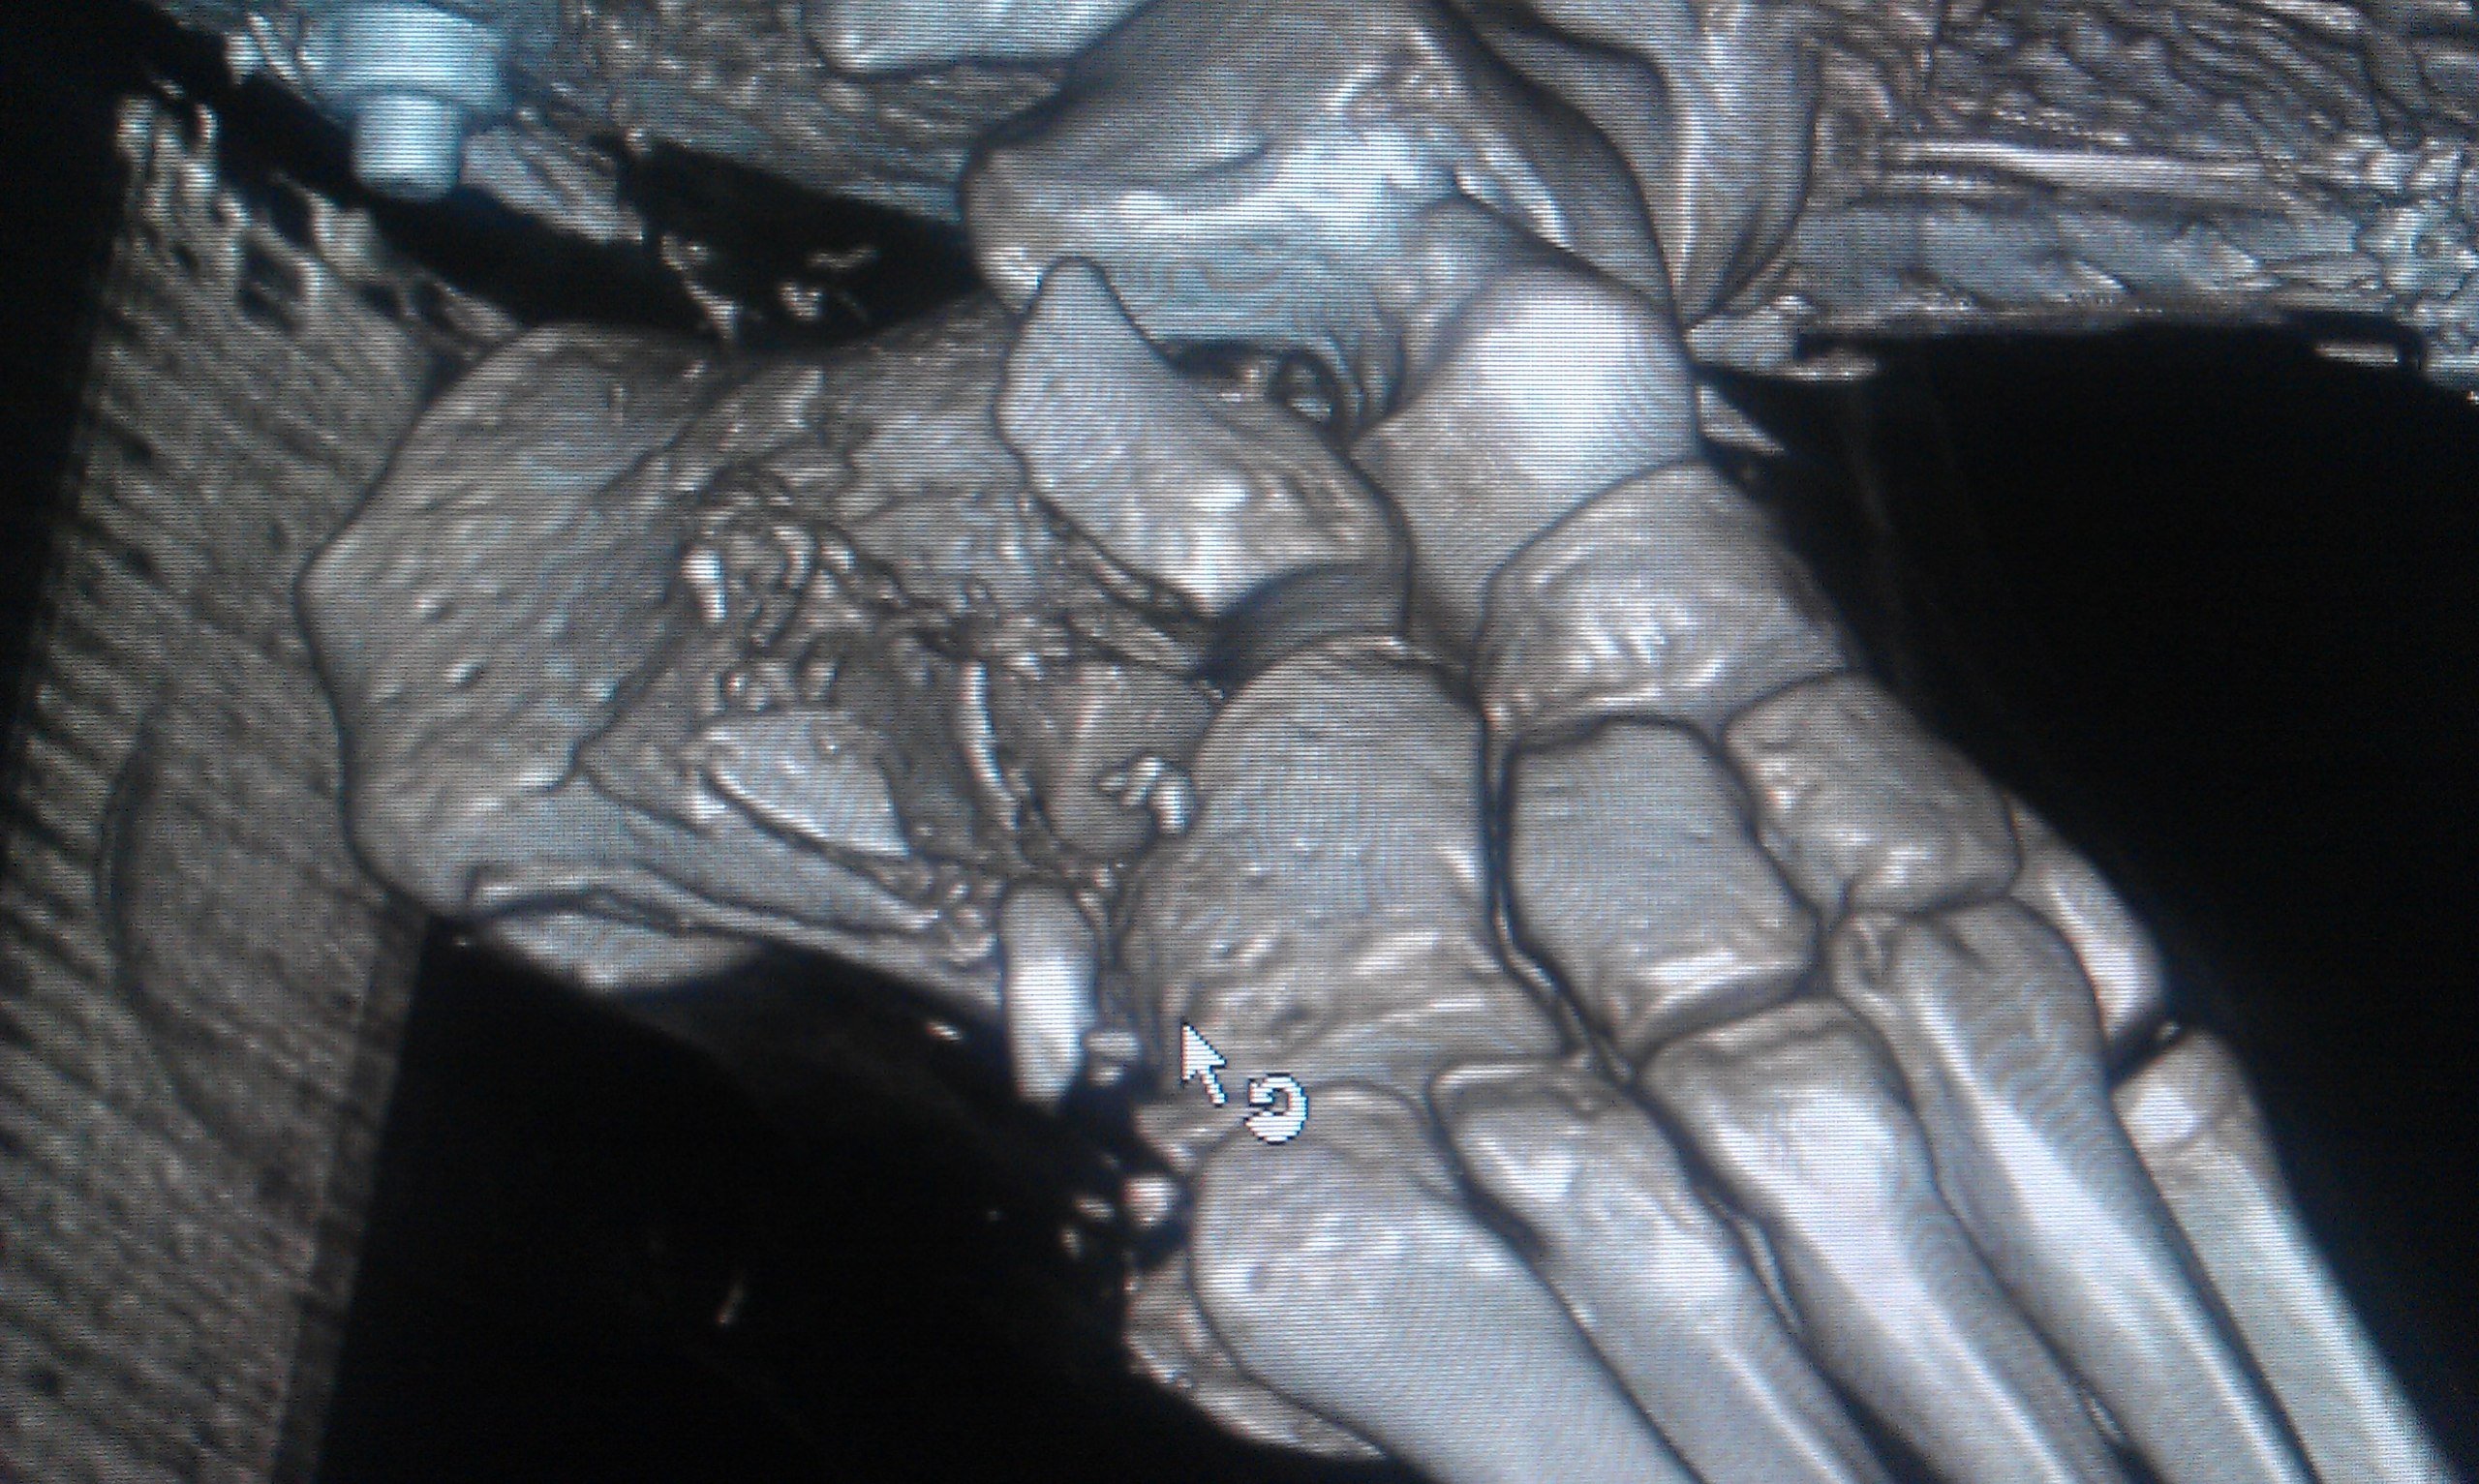

Эпикриз: Сочетанная травма. ЗЧМТ. Сотрясение головного мозга. Открытый многооскольчатый перелом обеих костей с/3 правой голени со смещением отломков. Открытый многооскольчатый перелом пяточной, ладьевидной, кубовидной кости, подвывих пяточной кости. Обширные рваные раны области правой стопы, правой голени.

было это еще 7 июня, но до сих пор, по прошествии двух операций ему не собрали все кости. Оказалосьь, что одну кость забыли на месте ДТП и теперь вместо нее требуется имплант. На одной ноге у него сейчас 18 переломов и 3 из них гниют, один из кусков кости встал поперёк, врачи опасаются её доставать или разворачивать, ибо можно занести ещё больше инфекции, если делать, то надо делать сразу всё комплексно, а пока приходится постоянно чистить, чтоб не было заражения, никакие обезболивающие уже не помогают, организм уже к ним адаптировался, и приходится терпеть эти боли. Нам же остается только медленно собирать деньги.